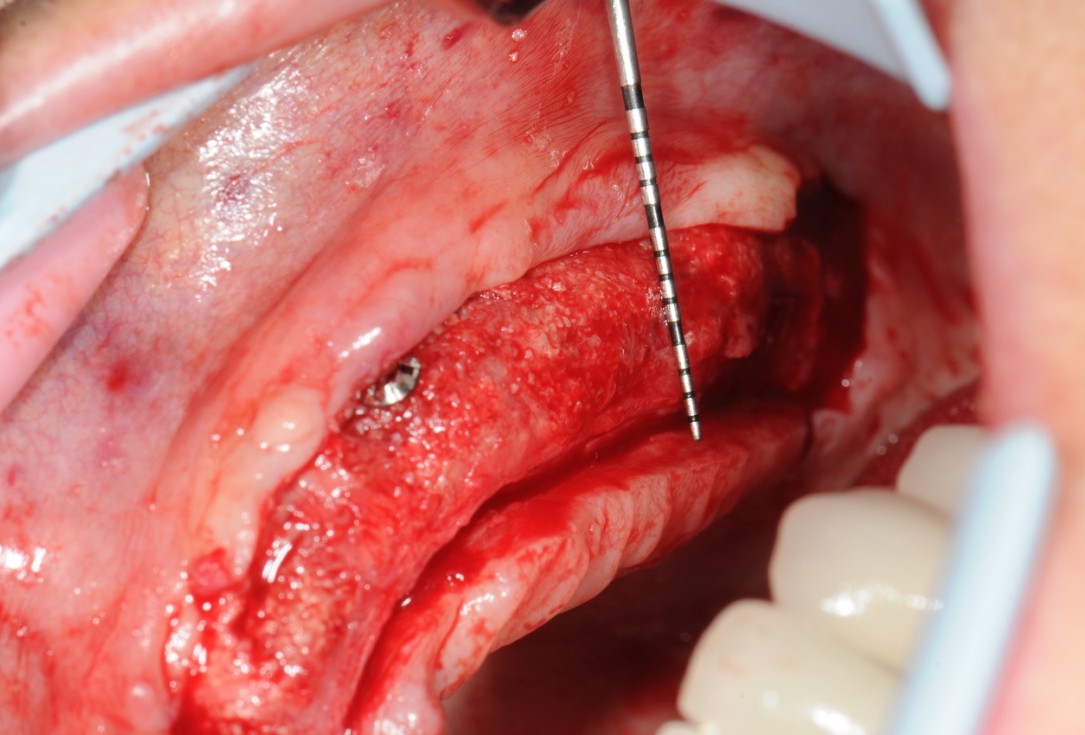

1/21 - Initial situation with severe maxillary atrophy